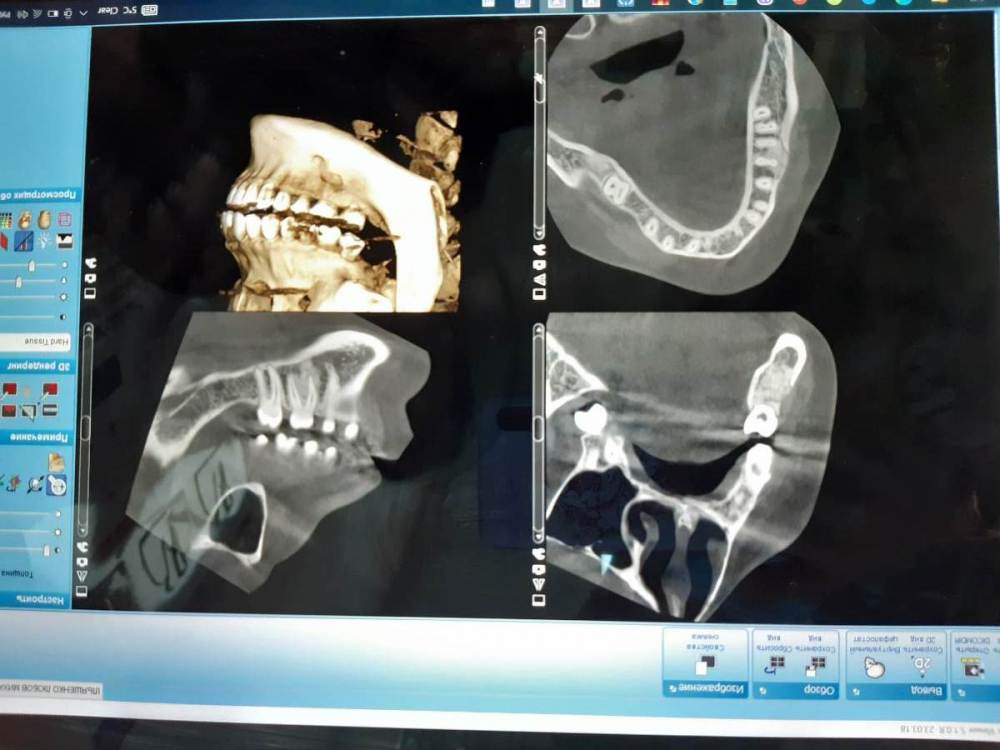

Lyubanya Опубликовано 8 октября, 2021 Поделиться Опубликовано 8 октября, 2021 (изменено) Коллеги, очень нужен ваш совет по поводу данного образования. Разница между снимками полгода. Симптоматики нет никакой. Кажется, есть тенденция к росту. Есть ли хоть шанс спасти зуб? Потеряла шестерку с другой стороны 10 лет назад, куча проблем теперь. Терять еще и этот уже как трагедия((( 31.03.21 7.10.21 Изменено 8 октября, 2021 пользователем Lyubanya Ссылка на комментарий

kriokov Опубликовано 13 октября, 2021 Поделиться Опубликовано 13 октября, 2021 20 часов назад, Lyubanya сказал: На холод реакция зуба есть) Рогацкина надо Вам активировать, он рентгенолог. На мой взгляд рентгенологически похоже и на цементно-костную дисплазию и на остеит. Ссылка на комментарий

Lyubanya Опубликовано 13 октября, 2021 Автор Поделиться Опубликовано 13 октября, 2021 8 часов назад, kriokov сказал: Рогацкина надо Вам активировать, он рентгенолог. На мой взгляд рентгенологически похоже и на цементно-костную дисплазию и на остеит. Рогацкина пинаю)) Были трудности с доступом файлов через гугл диск, потом поковыряла настройки и все наладилось. Пнула вчера, ответил что где-то в дороге. Пну завтра еще) Я тоже по снимкам тут, на форуме, посмотрела что на дисплазию похоже. Один из хирургов ставил остеому под ? Ссылка на комментарий

kriokov Опубликовано 13 октября, 2021 Поделиться Опубликовано 13 октября, 2021 3 часа назад, Lyubanya сказал: Рогацкина пинаю)) Были трудности с доступом файлов через гугл диск, потом поковыряла настройки и все наладилось. Пнула вчера, ответил что где-то в дороге. Пну завтра еще) Я тоже по снимкам тут, на форуме, посмотрела что на дисплазию похоже. Один из хирургов ставил остеому под ? не думаю, что остеома Ссылка на комментарий